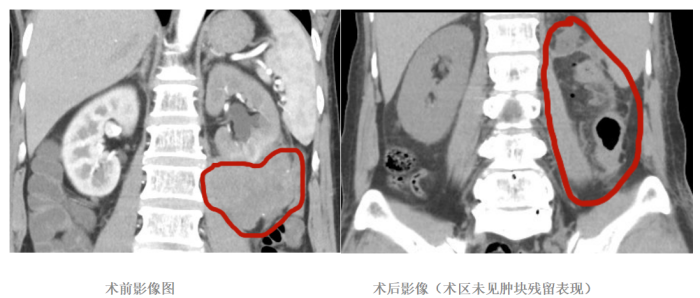

此次手术的患者为56岁市民,因腹腔内生长一颗直径达10厘米的腹膜后肿瘤,前往沿河人民医院就诊。经详细检查后,一个棘手的问题浮出水面:肿瘤与肠系膜、降结肠及左肾下极形成了广泛且复杂的粘连,更与腹主动脉紧密相连。这一病情意味着手术操作空间被严重压缩,术中稍有不慎便可能损伤周围重要脏器,不仅对主刀医生的临床经验、操作精度提出了极高要求,更考验着整个手术团队的协作默契度,手术难度与风险不言而喻。

手术当天,铜仁市人民医院帮扶专家凭借丰富的临床经验和精湛的手术技艺,在术中精准判断肿瘤粘连部位,与沿河人民医院手术团队紧密配合、无缝衔接。团队成员各司其职、默契协作,在小心翼翼分离粘连组织的同时,最大限度保护了周围脏器的正常功能。经过3个多小时的紧张奋战,终于成功将肿瘤完整切除,手术过程十分顺利。

术后,患者生命体征保持平稳,未出现任何并发症。在两院诊疗团队的精心治疗与细致护理下,患者恢复状况良好,目前已顺利出院,后续将按计划进行病情评估与综合治疗。

如今,在沿河分院的病房里,帮扶专家的教学查房每天都在进行;远程会诊中心随时连通铜仁总院,让基层患者实时享受到三级医院的诊疗服务。正如术后影像显示的“术区无肿瘤残留”,组团式帮扶正精准“切除”基层医疗的短板,为区域医疗卫生高质量发展注入持久动力。